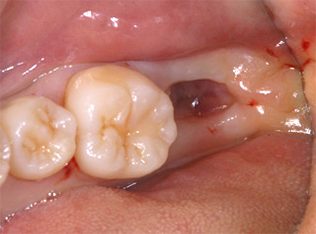

CASE

左下の一番奥歯が虫歯で抜歯となった30歳 女性

BEFORE

虫歯が大きく歯を残すことができずに抜歯となってしまいました。

レントゲンです。 向かって左端上の親知らずを、右下の奥に移植します。

AFTER

左の写真が親知らずを移植した直後のものです。 その後、根の治療をしクラウンを被せた状態の写真が右です。

移植後のレントゲンです。 BEFOREのレントゲンで空白だった部分におさまているのがわかると思います。